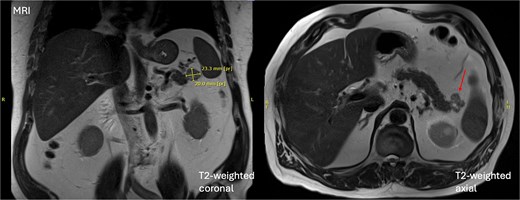

At the time of review, the patient was asymptomatic. Physical examination was unremarkable. A dedicated magnetic resonance imaging (MRI) demonstrated a 20 × 26 × 20 mm mixed solid and cystic lesion in the pancreatic tail with T1 hyperintensity, consistent with proteinaceous contents, but no interval growth since earlier imaging in 2020 (illustrated in Fig. 1). This stability favoured a benign aetiology, with pseudocyst or low-grade cystic neoplasm being the primary considerations. EUS-FNA was deemed unfeasible given the cyst’s location, and instead serial MRI imaging was arranged as per the Kyoto guidelines [2].

Initial MRI demonstrating a 20 × 26 × 20 mm mixed solid and cystic lesion in the pancreatic tail.